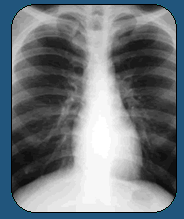

Doctors say Juarez's incessant hack was a sign of

what they have both dreaded and expected for years

-- this country's first case of a contagious, aggressive,

especially drug-resistant form of tuberculosis. The

Associated Press learned of his case, which until

now has not been made public, as part of a six-month

look at the soaring global challenge of drug resistance.

Juarez's strain -- so-called extremely drug-resistant

(XXDR) TB -- has never before been seen in the U.S.,

according to Dr. David Ashkin, one of the nation's

leading experts on tuberculosis. XXDR tuberculosis

is so rare that only a handful of other people in

the world are thought to have had it.

Juarez' strain of TB puzzled doctors. He had never

had TB before. Where did he pick it up? Had he passed

it on? And could they stop it before it killed him?

At first, mainstream doctors tried to treat him. But

the disease had already gnawed a golf-ball-sized hole

into his right lung.

When put side by side, his CAT scans from before and

after treatment are hard to believe. The dark hole

is gone, and only a small white scar tattoos his lung.